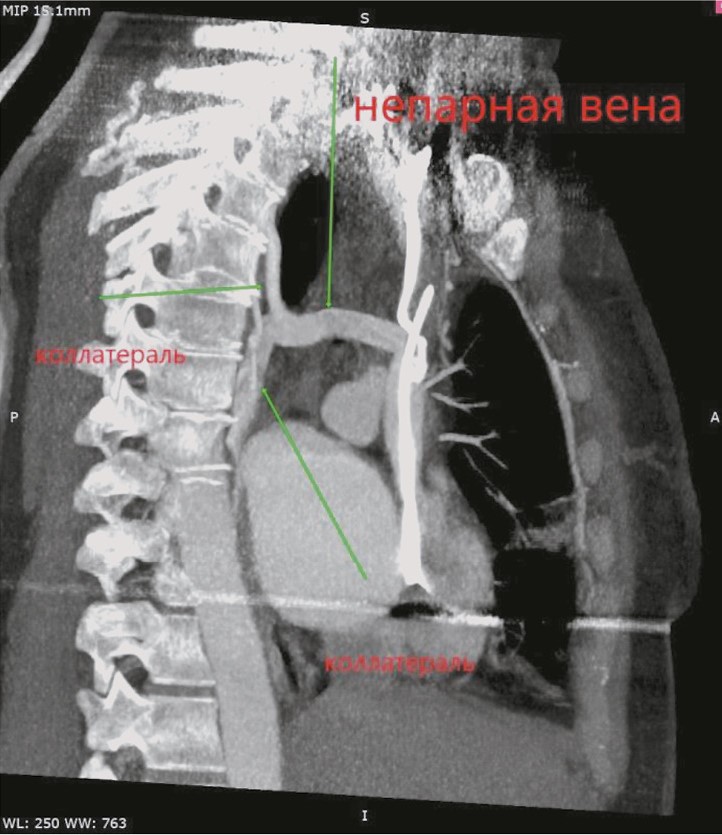

Рис. 3. Компьютерная томограмма пациентки К. Развитие коллатеральных анастомозов.

Fig. 3. Computed tomography of patient K. Development of collateral anastomoses.

Обращает на себя внимание выраженная задержка контраста в венах правой верхней конечности, куда вводилось контрастное вещество. Имеется богатая ветвь венозных анастомозов в мягких тканях грудной клетки, паравертебрально. ВПВ уменьшена в диаметре, её просвет практически полностью заполнен тромботическими массами от уровня впадения левой подключичной вены до места впадения непарной вены, сохранён просвет в виде узкой (1×4 мм) полулунной щели вдоль электрода. Непарная вена расширена, имеет диаметр до 10 мм и практически полностью обеспечивает верхний приток крови к правому предсердию. Основное возвращение крови к сердцу происходит через нижнюю полую вену, заполнение контрастом которой заметно отсрочено. Заключение: картина тромбоза/субтотальной облитерации ВПВ с организацией коллатерального венозного кровотока. Состояние после установки электрокардиостимулятора (ЭКС). Дилатация левых отделов сердца.